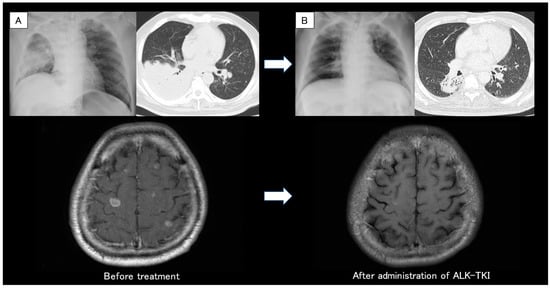

Figure 1. (A) Chest X-ray and head CT revealed the primary lung cancer at the right lower lobe with upper lobe atelectasis and multiple brain metastases. (B) Chest and head CT showed a favorable response after administration of molecular-targeted drugs for one month. CT: computed tomography. In the diagnosis of non-small cell lung cancer (NSCLC), the detection of driver gene mutations has become an essential test for treatment decisions [1]. On the other hand, as gene mutation panel tests need high-quality and adequate tissue samples, it can often be difficult to perform a gene batch analysis [2]. We reported that the lung cancer compact panel TM (LCCP), which was recently approved for use in Japan, was successful in detecting cases with epidermal growth factor receptor (EGFR) and MET gene mutations using sputum cytology [3]. However, as the quality of RNA tends to degrade quickly, it is generally recommended to use frozen or formalin-fixed, paraffin-embedded (FFPE) tissue specimens to secure a sufficient amount of nucleic acids. Conversely, if high-quality nucleic acid storage is available and high-sensitivity next-generation sequencing (NGS) can be implemented, it is possible to analyze RNA from cytological specimens. We report a case in which the echinoderm microtubule-associated, protein-like 4 anaplastic lymphoma kinase (EML4-ALK) fusion gene was detected in a sputum cytological specimen using LCCP (UMIN000047215/HREC ID 4814). This article is part of a prospective observational study of gene panel analysis using cytological specimens that is currently underway for patients with suspected lung malignancies. Cytological specimens such as transbronchial biopsy (TBB) brushing, transbronchial needle aspiration (TBNA), and pleural effusion were used for genetic panel testing. This study is ongoing since May 2020 (HREC ID 4814). Sputum was also an accepted sample in this study. Sputum and cytological specimens were collected in a sample container (GM tube, Genemetrics, Osaka, Japan) which contained a nucleic acid stabilizer, and they were processed with the Maxwell® RSC Blood DNA Kit and Maxwell® RSC Simply RNA Cells Kit (Promega, WI, USA). Using the purified nucleic acid, the LCCP TM (DNA Chip Research Inc., Tokyo, Japan) NGS assay was performed. The LCCP TM is an amplicon-based high-sensitivity NGS panel capable of measuring eight druggable genes (EGFR, BRAF, KRAS, ERBB2, ALK, ROS1, MET, and RET) for lung cancer. The LCCP was recently approved for clinical practice in Japan as a companion diagnostic kit. Analytical performance, clinical validity, and details of the analysis of the LCCP were previously reported [4]. The patient was a 67-year-old man who had never smoked but had a history of hypertension and type 2 diabetes. A family member found him collapsed in his bathroom, and an ambulance was called. Generalized tonic convulsion was also present during emergency transport. After arriving at the hospital, endotracheal intubation and mechanical ventilation were performed. The CT revealed multiple brain metastases (12 mm or less, 20 or more sites), a mass of more than 10 cm in the lower right lobe, and atelectasis in the upper right lobe (A). It was presumed that the seizure was associated with the brain metastases from the primary lung cancer. Tumor markers were CEA 18.8 ng/mL, SLX 1160 U/mL, CYFRA 11.2 ng/mL, SCC 4.2 ng/mL, ProGRP 74.5 pg/mL, and NSE 39.5 ng/mL. Since his condition stabilized with anticonvulsants and sedatives, he was extubated on hospital day 4 and was transferred to our respiratory medicine department. The next day, the sputum that he coughed up was cytologically positive for class Ⅴ adenocarcinoma (Figure 2A), and EGFR cobas® (liquid) was negative. The primary right lower lobe lung adenocarcinoma was considered to be T4N3M1c and c-stage IVB. A CT-guided biopsy was performed on day 7 for tissue sampling (Figure 2B). Whole-brain irradiation was initiated on the same day for multiple symptomatic brain metastases (30 Gy/10 Fr). NGS analysis (LCCP) of the CT-guided biopsy tissue revealed EML4-ALK positive on day 15, and immunohistochemical (IHC) staining/fluorescence in situ hybridization (FISH) confirmed each positive finding (Figure 2C,D). First-line brigatinib of 90 mg/day was administered on day 18, and the dose was increased to 180 mg/day after one week. Both the primary tumor and brain metastases showed remarkable improvements after one month (B) with CT assessment. Sputum collected on day 4 for LCCP analysis was successful in the detection of the EML4-ALK fusion gene (Figure 3). The detected RNA mutational variants extracted from tissues and sputum matched EML4exon6ins33_ALKexon20.